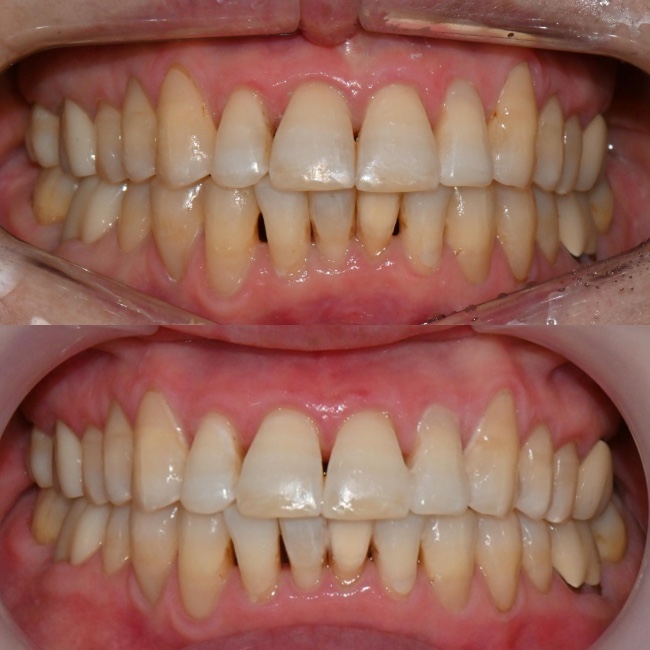

8개월 후 교정 치료가 마무리되었으며, 환자분께서 치아가 예쁘게 마무리되셨다며 매우 만족하셨습니다. 치간 삭제를 통해 black triangle도 일부 개선되었습니다. 미백 치료에도 관심이 있으셔서 2주 뒤 내원하셔서 미백 치료도 시행하셨습니다.

치료 전후 비교

미백치료 전후